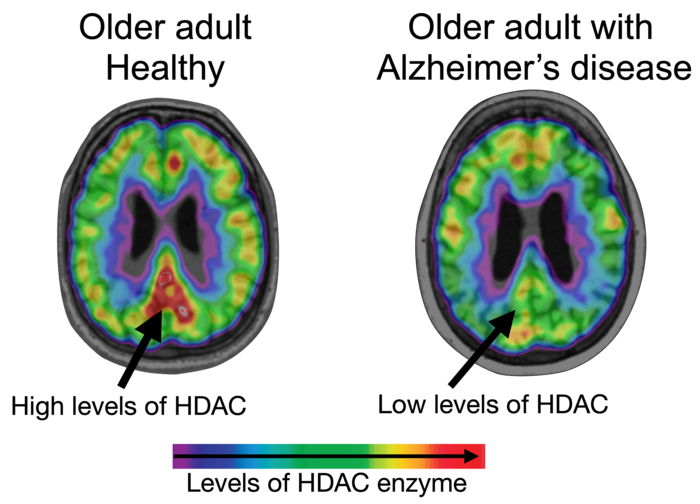

PITTSBURGH, July 19, 2022 – Contrary to early studies, brain levels of enzymes that regulate DNA-folding drop as Alzheimer’s disease progresses, neuroscientists from the University of Pittsburgh , McGill University , and Harvard University reported today in Nature Communications .

These dogma-challenging findings, verified across two independent cohorts of live patients with Alzheimer’s disease and on post-mortem brain tissues, show that reduced levels of Histone Deacetylase I (HDAC I)—one of the enzymes that regulate how DNA is packaged inside the cell’s nucleus—are linked to deleterious effects of misfolded beta-amyloid and tau proteins and Alzheimer’s-associated cognitive decline.

Using a selective molecular tracer called [11C]Martinostat, researchers showed that HDAC I levels were greatly reduced in the brains of people with Alzheimer’s disease compared to non-Alzheimer’s controls, specifically in regions buried deep inside the brain’s core – hippocampus and the midline -- as well as in the brain’s temporal cortex.

Analyses showed that reduced HDAC I in areas of the brain that are most susceptible to Alzheimer’s disease-associated degenerative changes corresponded to higher beta-amyloid and tau burden. It also predicted progressive neurodegeneration and cognitive decline over the two-year period.